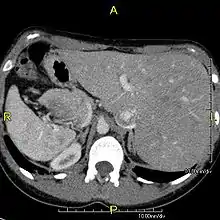

The condition affects all major structures within the thorax and abdomen. Generally, the organs are simply transposed through the sagittal plane. The heart is located on the right side of the thorax, the stomach and spleen on the right side of the abdomen and the liver and gall bladder on the left side. The heart's normal right atrium occurs on the left, and the left atrium is on the right. The lung anatomy is reversed and the left lung has three lobes while the right lung has two lobes. The intestines and other internal structures are also reversed from the normal, and the blood vessels, nerves, and lymphatics are also transposed.

If the heart is swapped to the right side of the thorax, it is known as "situs inversus with dextrocardia" or "situs inversus totalis". If the heart remains on the normal left side of the thorax, a much rarer condition (1 in 2,000,000 of the general population), it is known as "situs inversus with levocardia" or "situs inversus incompletus".

Diagnosis of situs inversus can be made using imaging techniques such as x-ray, ultrasound, CT scan, and magnetic resonance imaging (MRI).[7]